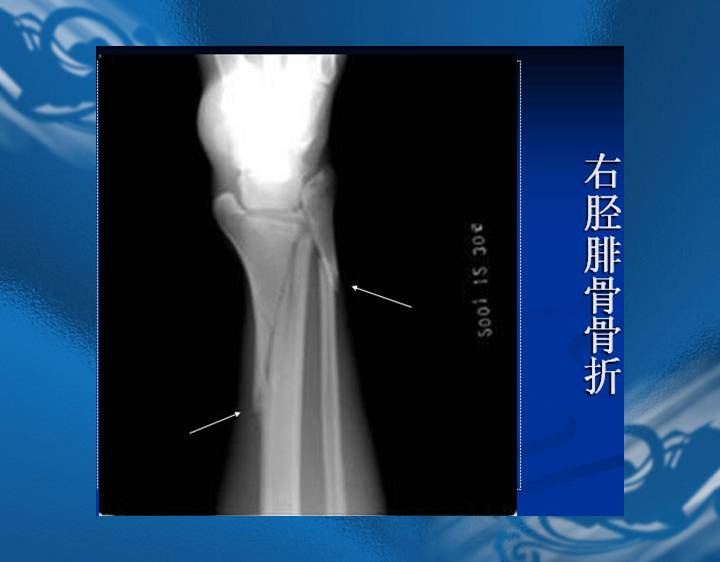

执业医师资格考试“实践技能”影像学辅导资料